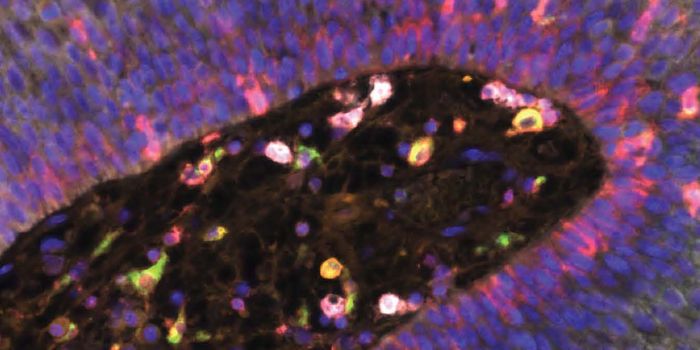

AUG 26, 2024Clinical & Molecular DXA colorized scanning electron micrograph depicts a Kupffer cell. / Credit: Thomas Deerinck, National Center for Microsco ...